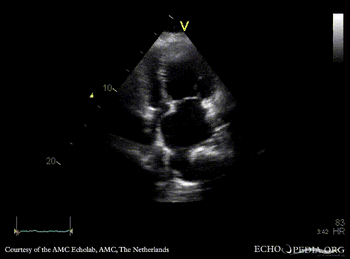

| Courtesy of: AMC Echolab, AMC, The Netherlands | |

| A4CH: dilated pulmonary veins | A4CH with Color Doppler |